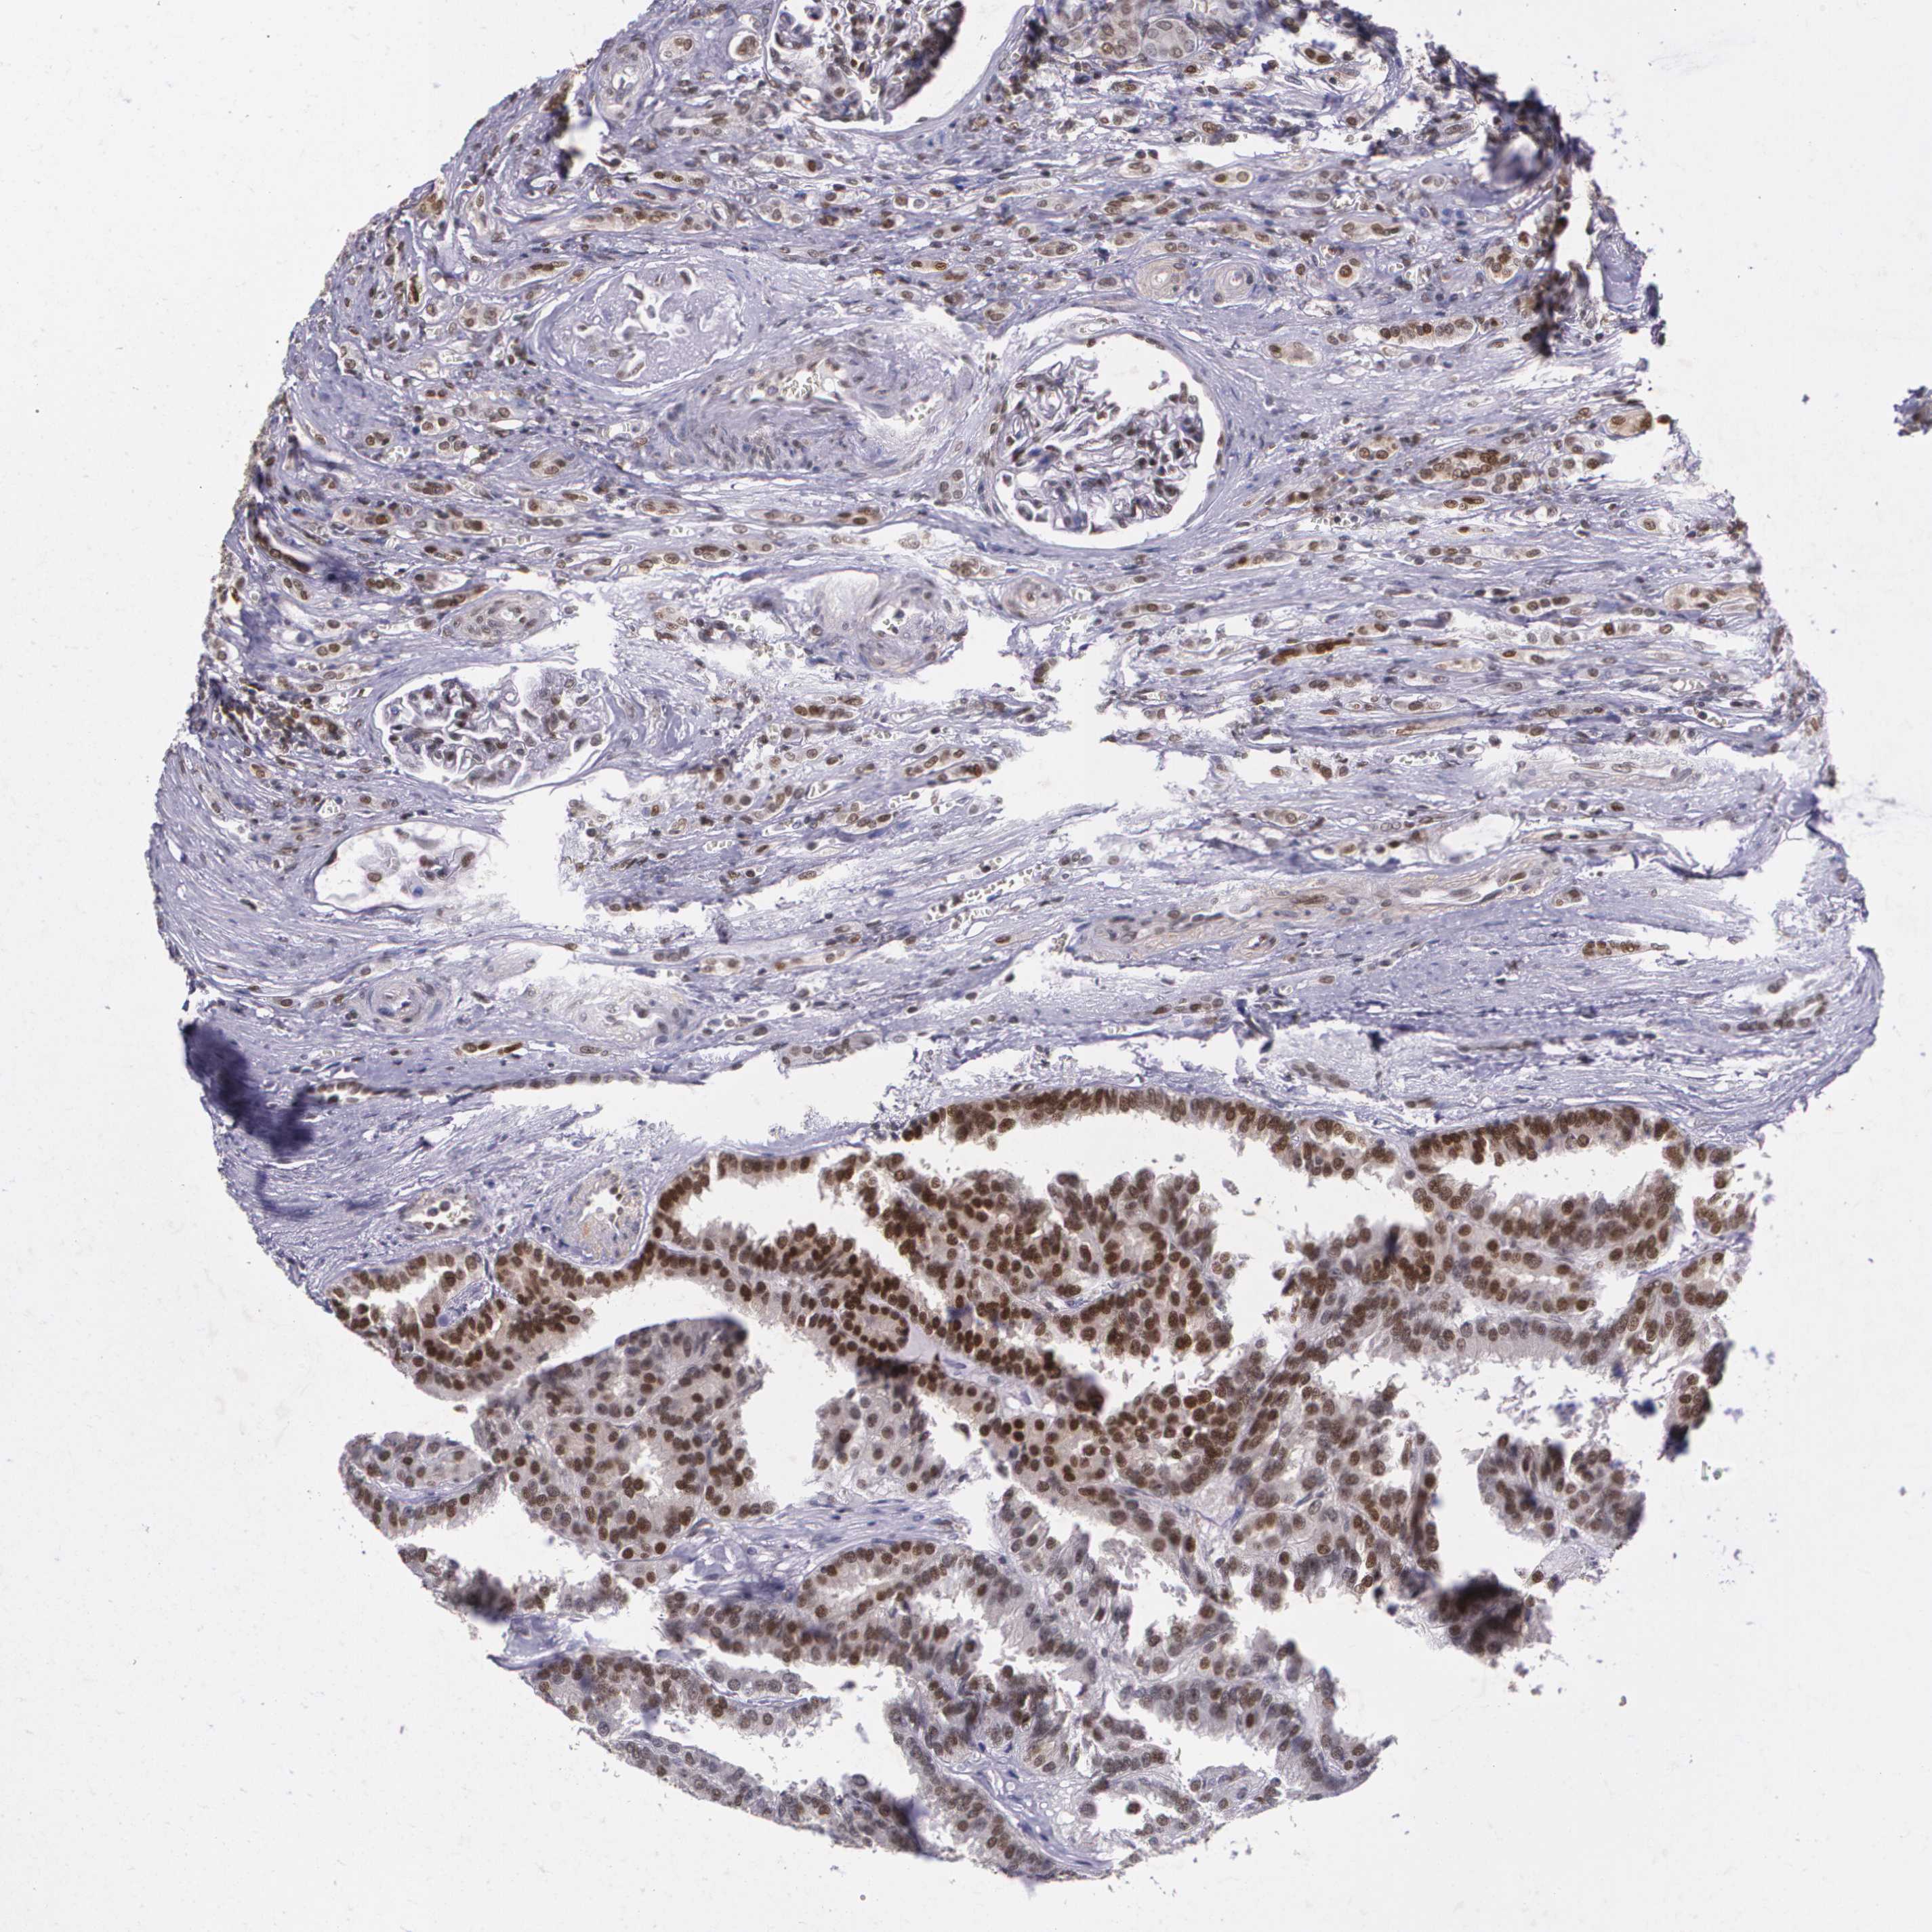

MGMT